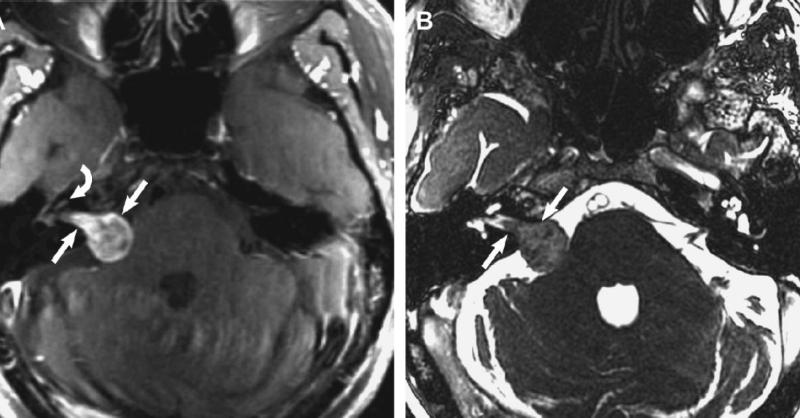

Cerebellopontine angle (CPA) is a triangular space in the posterior cranial fossa that is bounded by the tentorium superiorly, brainstem posteromedially and petrous part of temporal bone posterolaterally. It is an important landmark anatomically and clinically as it is occupied by the CPA cistern, which houses the cranial nerve V, VI, VII, and VIII

Cerebellopontine Angle (CPA) Tumor